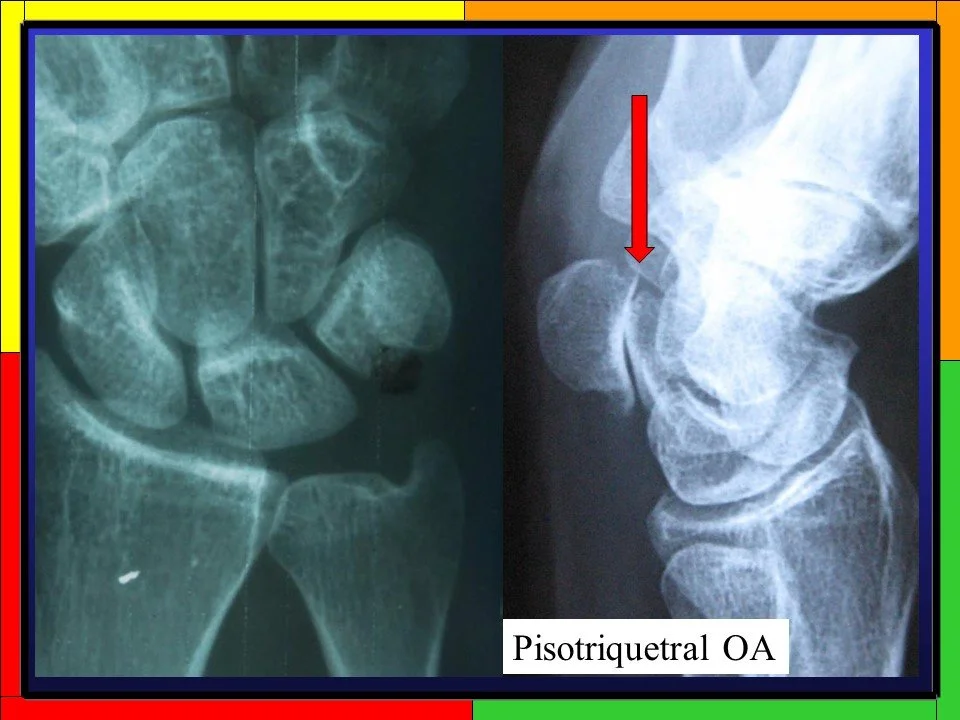

Arthritis

Radiographers